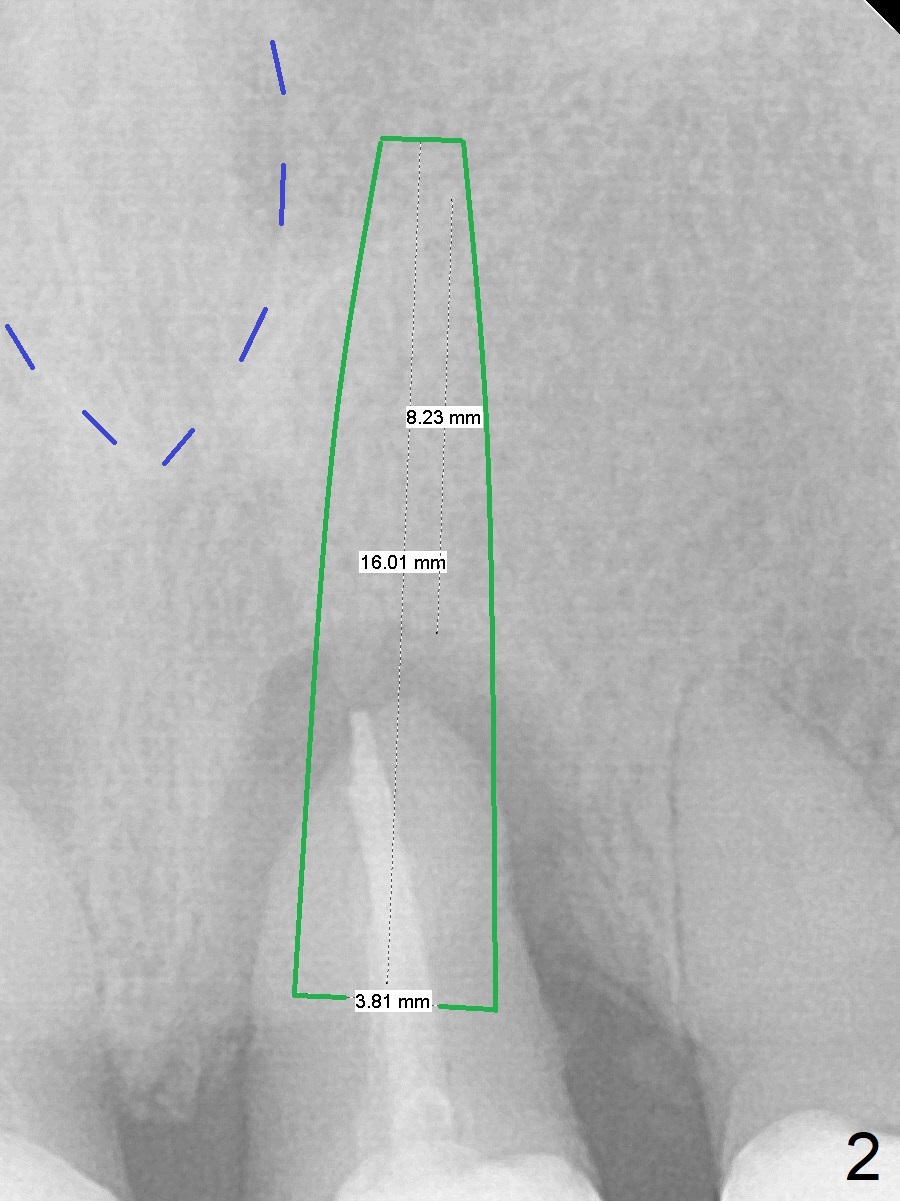

A 61-year-old woman returns with chief complaint of "loose tooth" at #9 nine month post cementation at #7 (Fig.1 (periradicular radiolucency (*)). Because of lack of posterior support, a long implant will be placed immediately post extraction (Fig.2). Be careful of the nasal floor, which is slanted (Fig.1 red dashed line). It seems that the implant at the central incisor would be shorter than that at the lateral one. The diameter should be the same. Take PA after 2 mm drill to avoid the Incisive Foramen (Fig.2 blue dashed line).